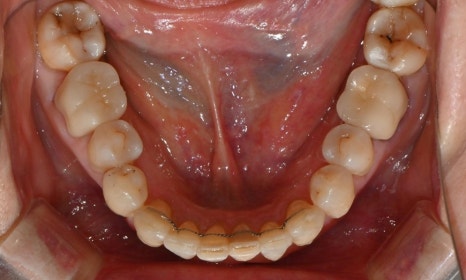

본 환자는 70세 여환으로 가만히 입을 다물고 있을 때 화난 것 처럼 보인다고 해서 튀어나온 앞니를 조금 넣고 싶다는 주소로 내원하셨습니다. 전체적인 치아 및 잇몸 상태를 검진해본 결과, 마모되어 깨진 치아도 있었고, 치경부(치아와 잇몸 사이 경계 부위)가 마모되어 파여 있는 부위도 많았습니다.

2025.2.3. 초진

교정 치료를 시작하기 전에 위아래 깨진 어금니는 보철 치료를 시행하였고, 치경부는 레진 치료를 시행하였습니다. 거의 뿌리의 신경관 근처까지 파여있던 치아가 치경부 레진 치료로 자연스럽게 수복이 되었습니다.

치경부 레진 치료 전후